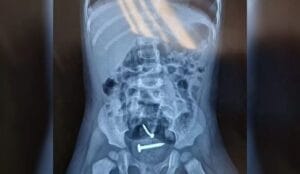

Exames apontam parafusos dentro de criança de 1 ano que era estuprada pelo próprio pai